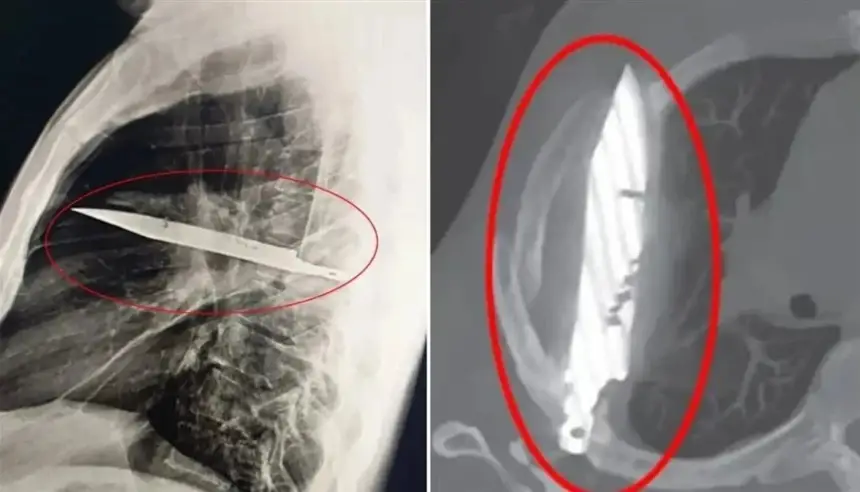

وأظهرت الفحوص بالأشعة وجود جسم معدني ضخم اخترق جسده عبر لوح الكتف الأيمن واستقر على مسافة خطيرة من أعضائه الحيوية، من دون أن يلحظ الأمر طوال هذه السنوات. وذكر المريض أنه أصيب في وجهه وظهره وصدره وبطنه خلال مشاجرة عنيفة قبل نحو عقد، وتلقى علاجاً حينها، لكنه لم يكن يعلم أن السكين بقي عالقاً داخل جسده.

وأجرى الجراحون عملية دقيقة لاستخراج السكين وتصريف الصديد الناتج عن تلف الأنسجة، وقضى المريض 24 ساعة في العناية المركزة ثم 10 أيام في الجناح العام قبل أن يتعافى ويغادر المستشفى. ووصفت Journal of Surgical Case Reports الحالة بأنها من أندر الوقائع التي ينجو فيها مريض رغم بقاء جسم غريب بهذا الحجم داخل جسده لسنوات.